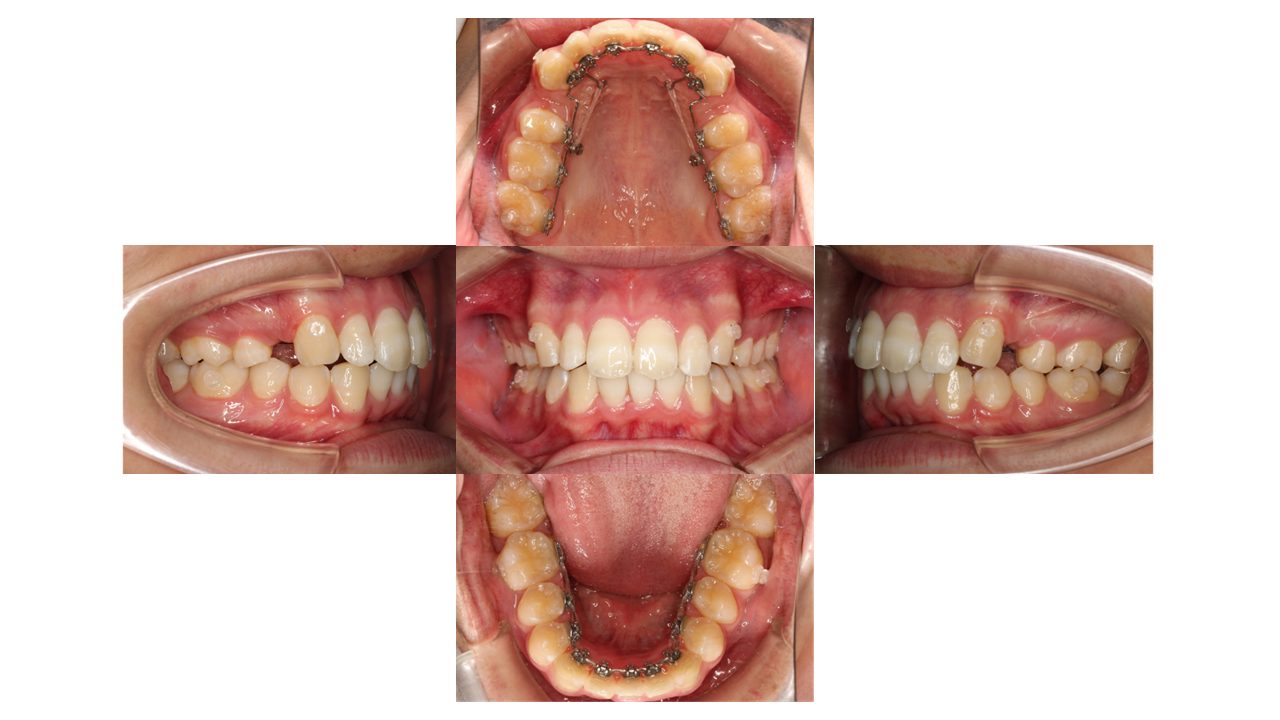

6ヵ月経過の口腔内の状態です。

上顎に歯科用アンカースクリューを埋入し、ゴムの力を使って前歯を引っ張りながら抜歯したスペースを閉じていきます。